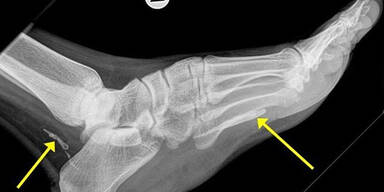

Parasit ernährte sich von Fleisch, wurde am Röntgen entdeckt.

Einem 38-jährigen Mann haben Ärzte in Australien einen meterlangen Bandwurm aus dem Fuß entfernt. Der Parasit ernährte sich vom Fleisch, und soll mindestens 4 Jahre lang im Körper des Mannes gelebt haben. Auf Röntgenaufnahmen, die das St. Vincent's Hospital (Sydney) veröffentlicht hat, sind die Überreste des Fadenwurms deutlich zu sehen.